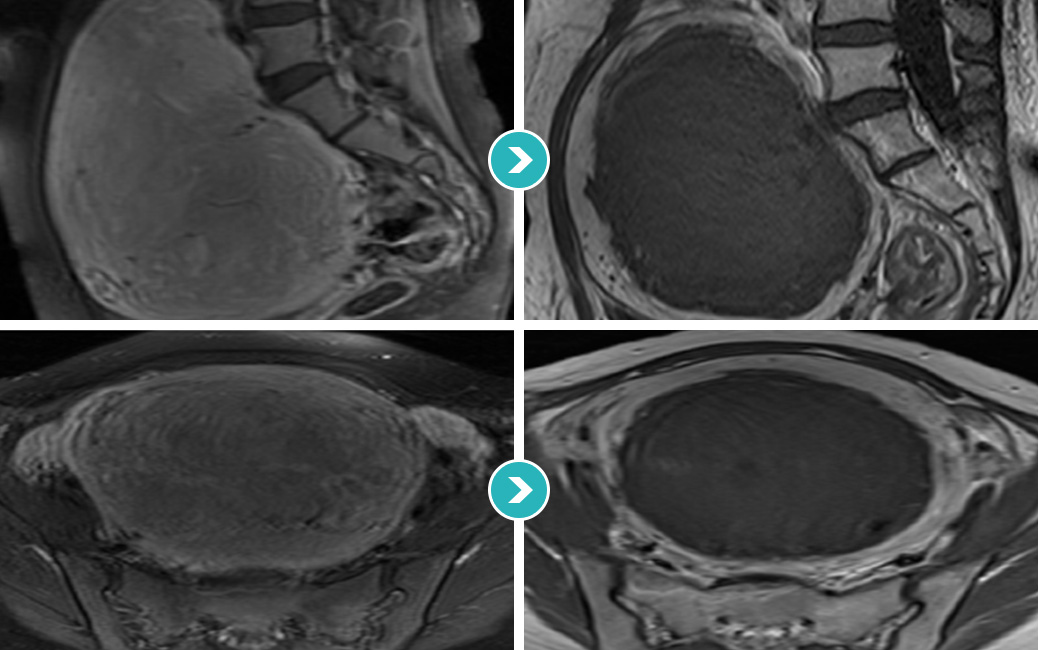

질출혈과 생리과다 및 복부에만져지는 거대 자궁근종으로 자궁근종 하이푸 치료를 위해 내원하였습니다.

하이푸 시술전 MRI사진상 척추와 복벽을 밀고있는 14cm의 혈류가 풍부한 거대 자궁근종이 관찰됩니다. 자궁근종 하이푸 치료는 자궁근종 부위만 선택적으로

치료하는 시술로 자궁근종 전체적으로 자궁근종 하이푸 치료하였고, 14cm 거대 자궁근종 하이푸 치료시간은 164분이 소요되었습니다.

(Uterine Myoma Hifu treatment time 164min)